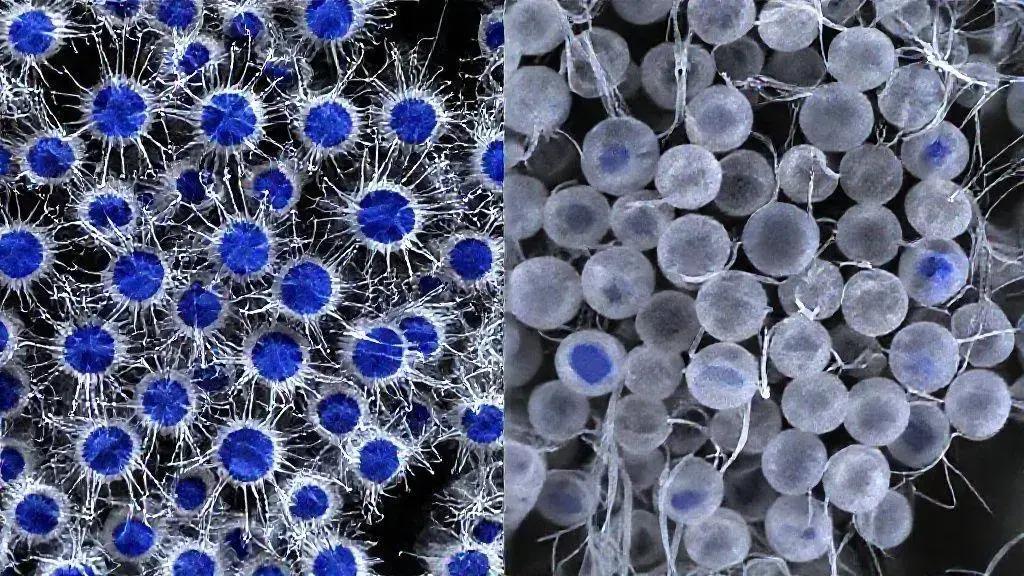

A origem exata do neuroblastoma ainda é estudada. Sabemos que ele começa quando os neuroblastos não amadurecem como deveriam. Em vez de se tornarem células nervosas saudáveis, eles crescem de forma descontrolada. Isso forma um tumor. Na maioria dos casos, o neuroblastoma não é hereditário. Ou seja, não passa de pais para filhos. Ele surge de mutações genéticas que acontecem por acaso. Essas mutações fazem com que as células se comportem de maneira anormal.

Como o Neuroblastoma se Desenvolve no Corpo

As células do neuroblastoma podem ser muito agressivas. Elas têm a capacidade de se espalhar rapidamente para outras partes do corpo. Isso é chamado de metástase. Os locais mais comuns para a metástase são os ossos, a medula óssea, os gânglios linfáticos e o fígado. Quando o câncer se espalha, o tratamento se torna mais complexo. Por isso, um diagnóstico precoce é crucial. Ele pode fazer uma grande diferença no resultado do tratamento.